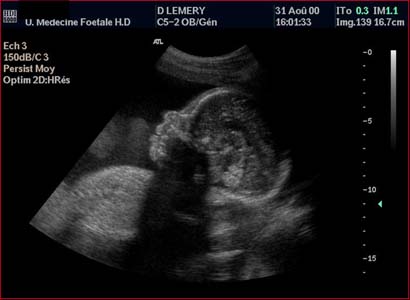

Front plat légèrement fuyant